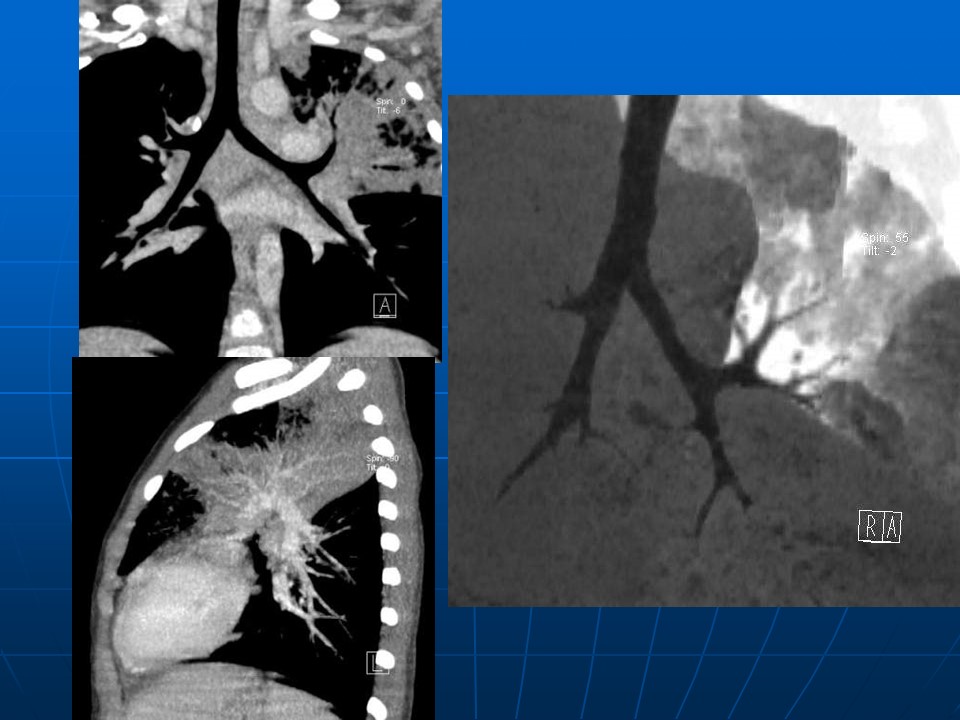

下一篇:【病例】肺动脉静脉畸形1例CT